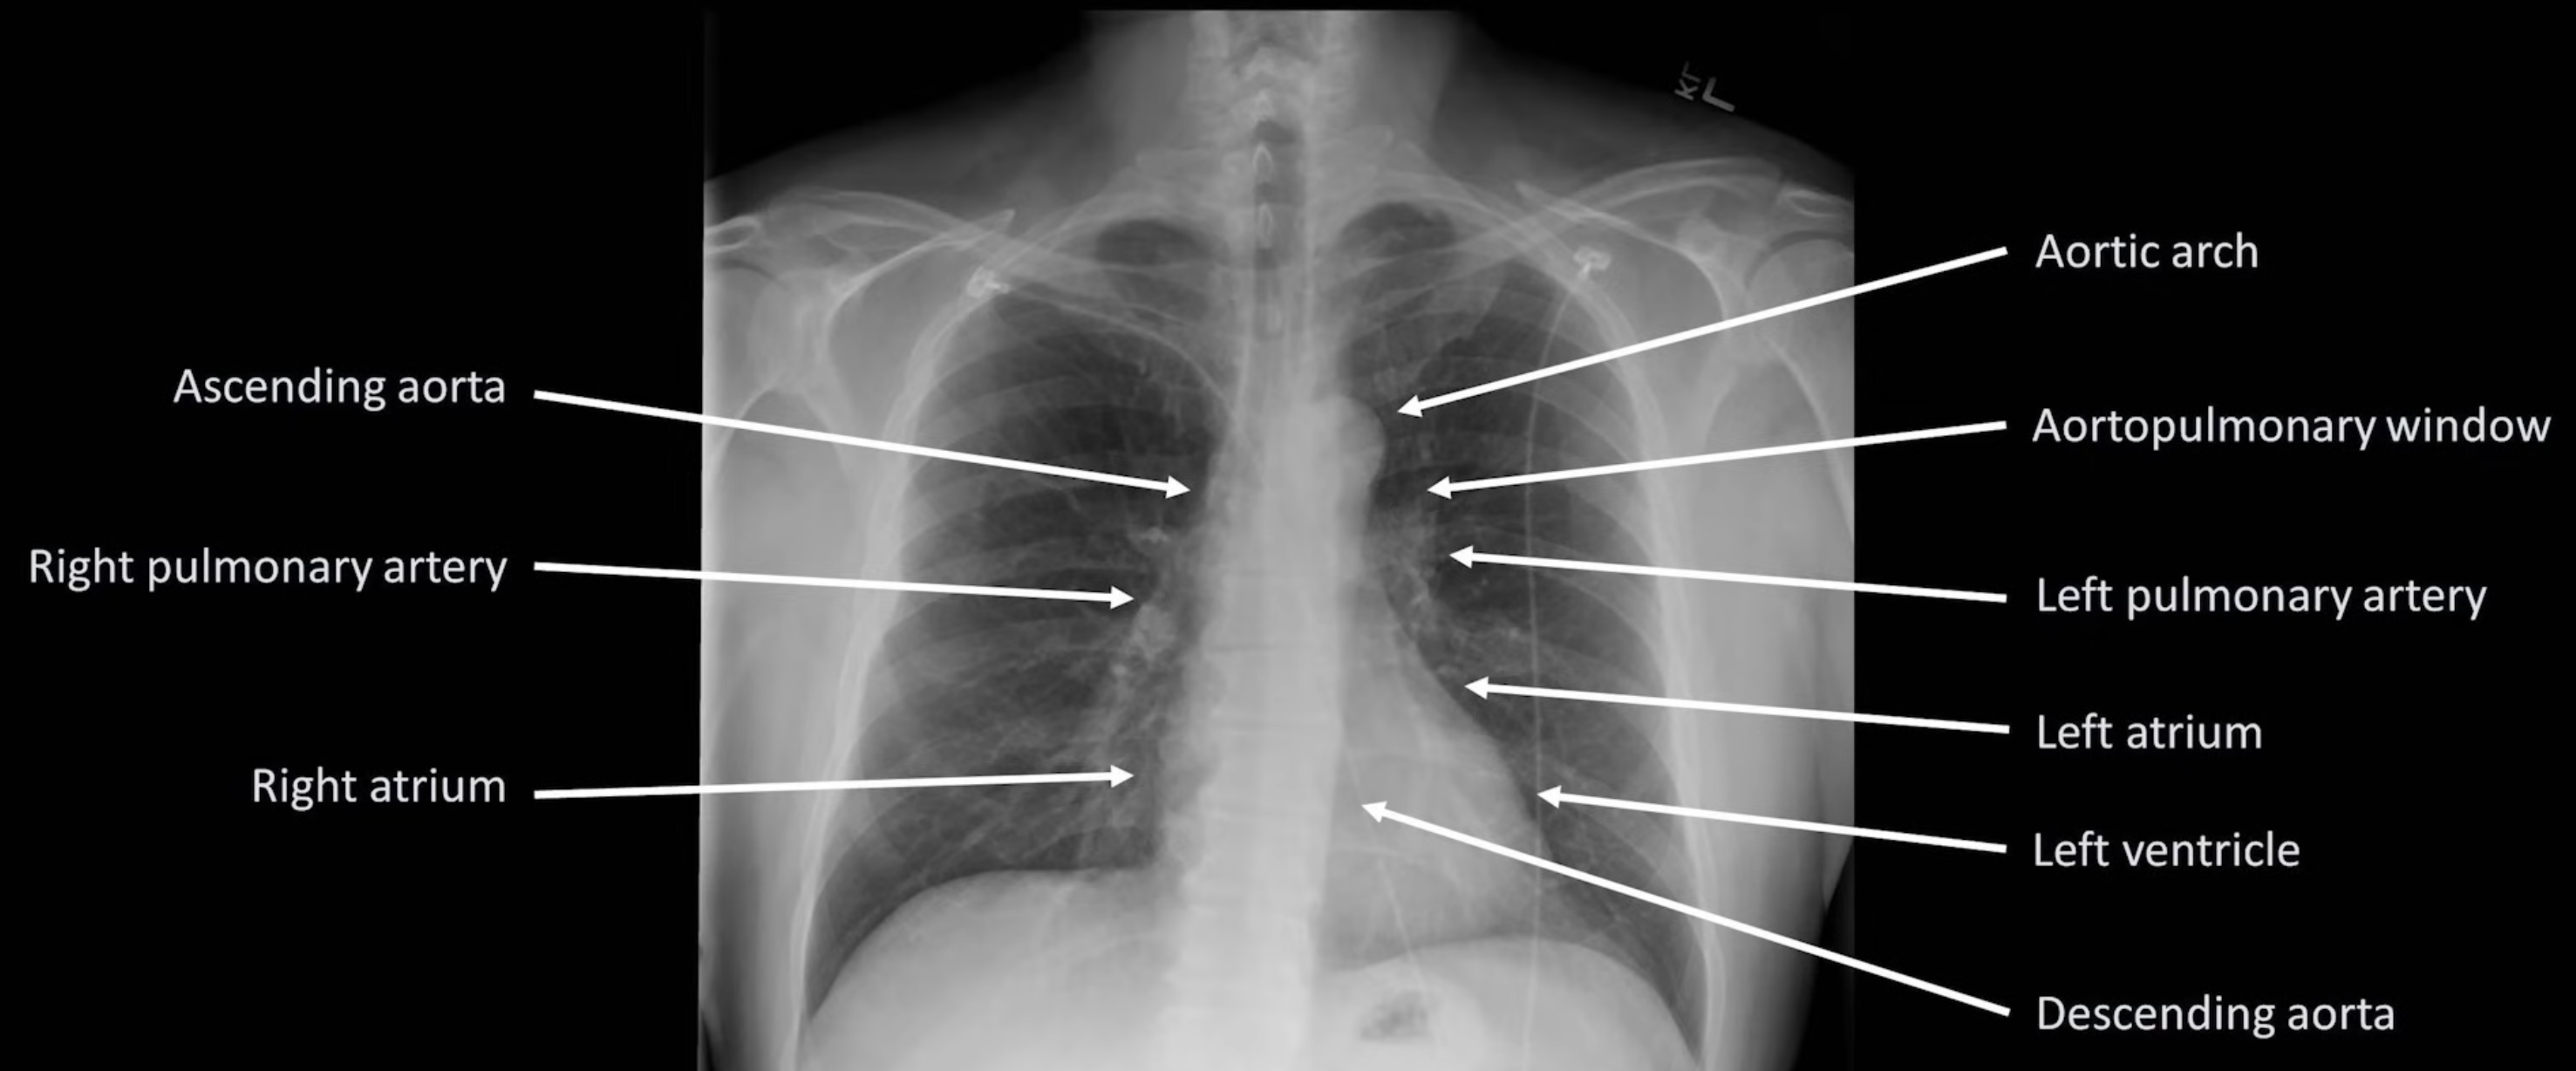

Anatomy

Cardiac Silhouette and Mediastinum

- Widened mediastinum is defined as >8cm.

Hilar Enlargement — Differentials

- Malignancy: primary lung cancer, lymphoma, metastatic disease

- Infection: tuberculosis, viruses (e.g. EBV)

- Other: sarcoidosis, silicosis, pulmonary hypertension, pulmonary artery aneurysm, bronchogenic cyst